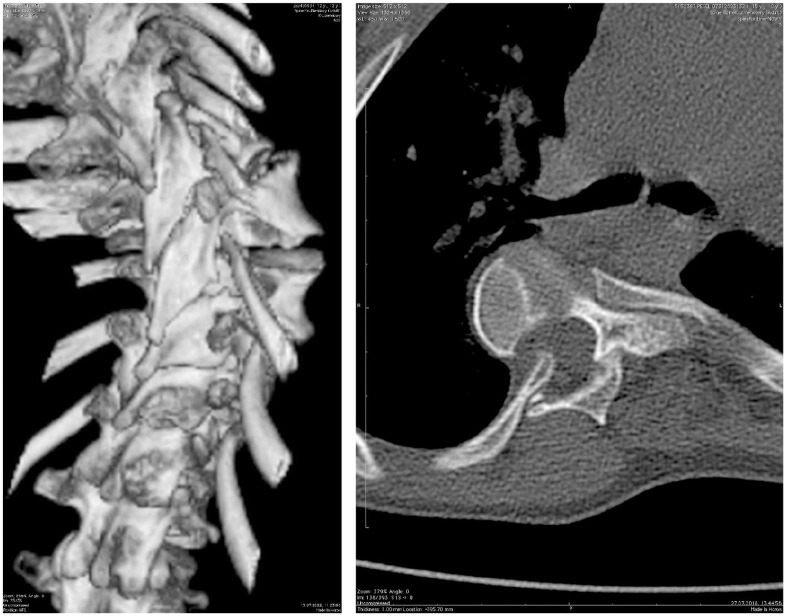

Abstract Image